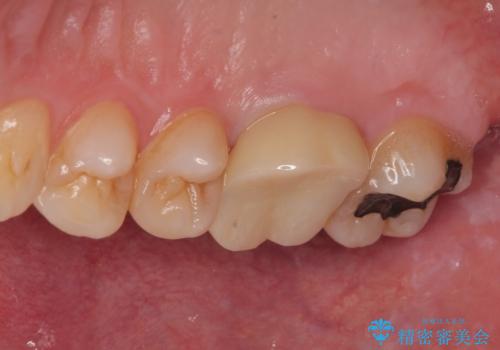

拡大鏡視野下で詰め物と虫歯の除去を行い、詰め物の範囲が大きかったためオールセラミッククラウンに適した形に整えました。

型どりはシリコーン印象材にて精密印象をしています。

痛みもなく、適合もよく、機能的に問題もなく、見た目も満足されていました。

嚙む力(咬合力)がとても強い方なのでナイトガードを今後使っていただく予定です。